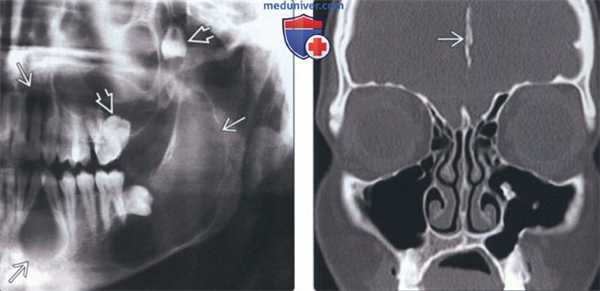

(Слева) На кадрированной панорамной рентгенограмме визуализируются как минимум четыре кистозных образования челюстей слева. В задних отделах верхней челюсти смещенные моляры видны отчетливее, чем очаг. Множественные очаги в челюстях, напоминающие кисты, подозрительны на синдром базальноклеточного невуса (СБКН).

(Справа) На корональной КТ в костном окне у пациента с СБКН определяется обызвествление серповидной связки мозга. Эта находка считается нормальной, тем не менее, у пациентов с СБКН она обнаруживается намного раньше.